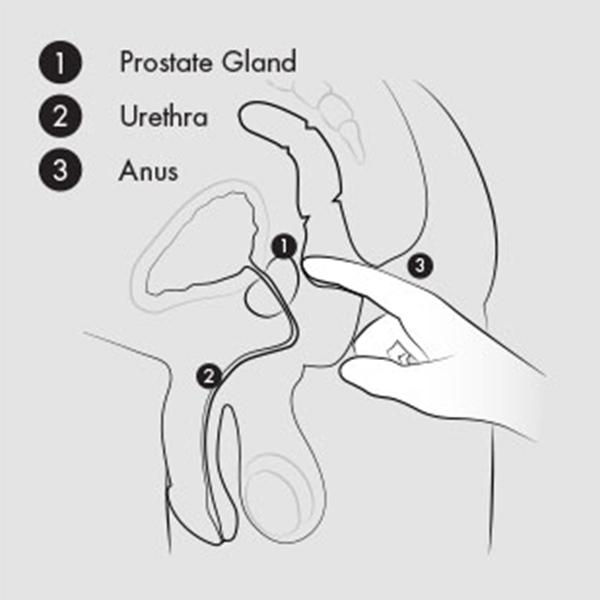

Dankzij de revolutionaire Multi-Axial Motion Architecture (MAMA) beweegt de Eupho Trident vrij in meerdere richtingen: zijwaarts, op en neer én roterend. Elke contractie van je bekkenbodemspieren zet de stimulator in beweging, waardoor een golf van sensaties ontstaat die je prostaat en anale kanaal verfijnd masseren.

Tijdens geslachtsgemeenschap komt de Eupho Trident pas écht tot leven: de slanke body beweegt vrij mee met de stoten van je partner, waardoor je orgasmes dieper, krachtiger en langer worden. De gebogen kop raakt je prostaat direct, terwijl de perineum-tab en de Kundalini-tab externe stimulatie toevoegen – samen goed voor een orkest van prikkels dat je hele lichaam laat meetrillen.